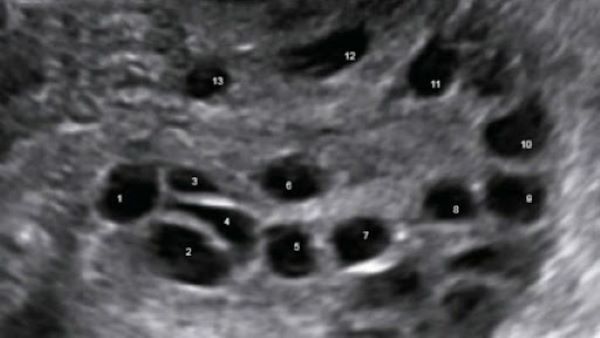

Tiêu chuẩn chẩn đoán buồng trứng đa nang trên siêu âm bao gồm: siêu âm ngày thứ 2 – 5 của chu kỳ kinh hoặc ngày thứ 3 của chu kỳ nhân tạo là có 12 nang kích thước từ 2 – 9mm và tăng thể tích buồng trứng >10cm3, thể hiện ít nhất ở một buồng trứng.